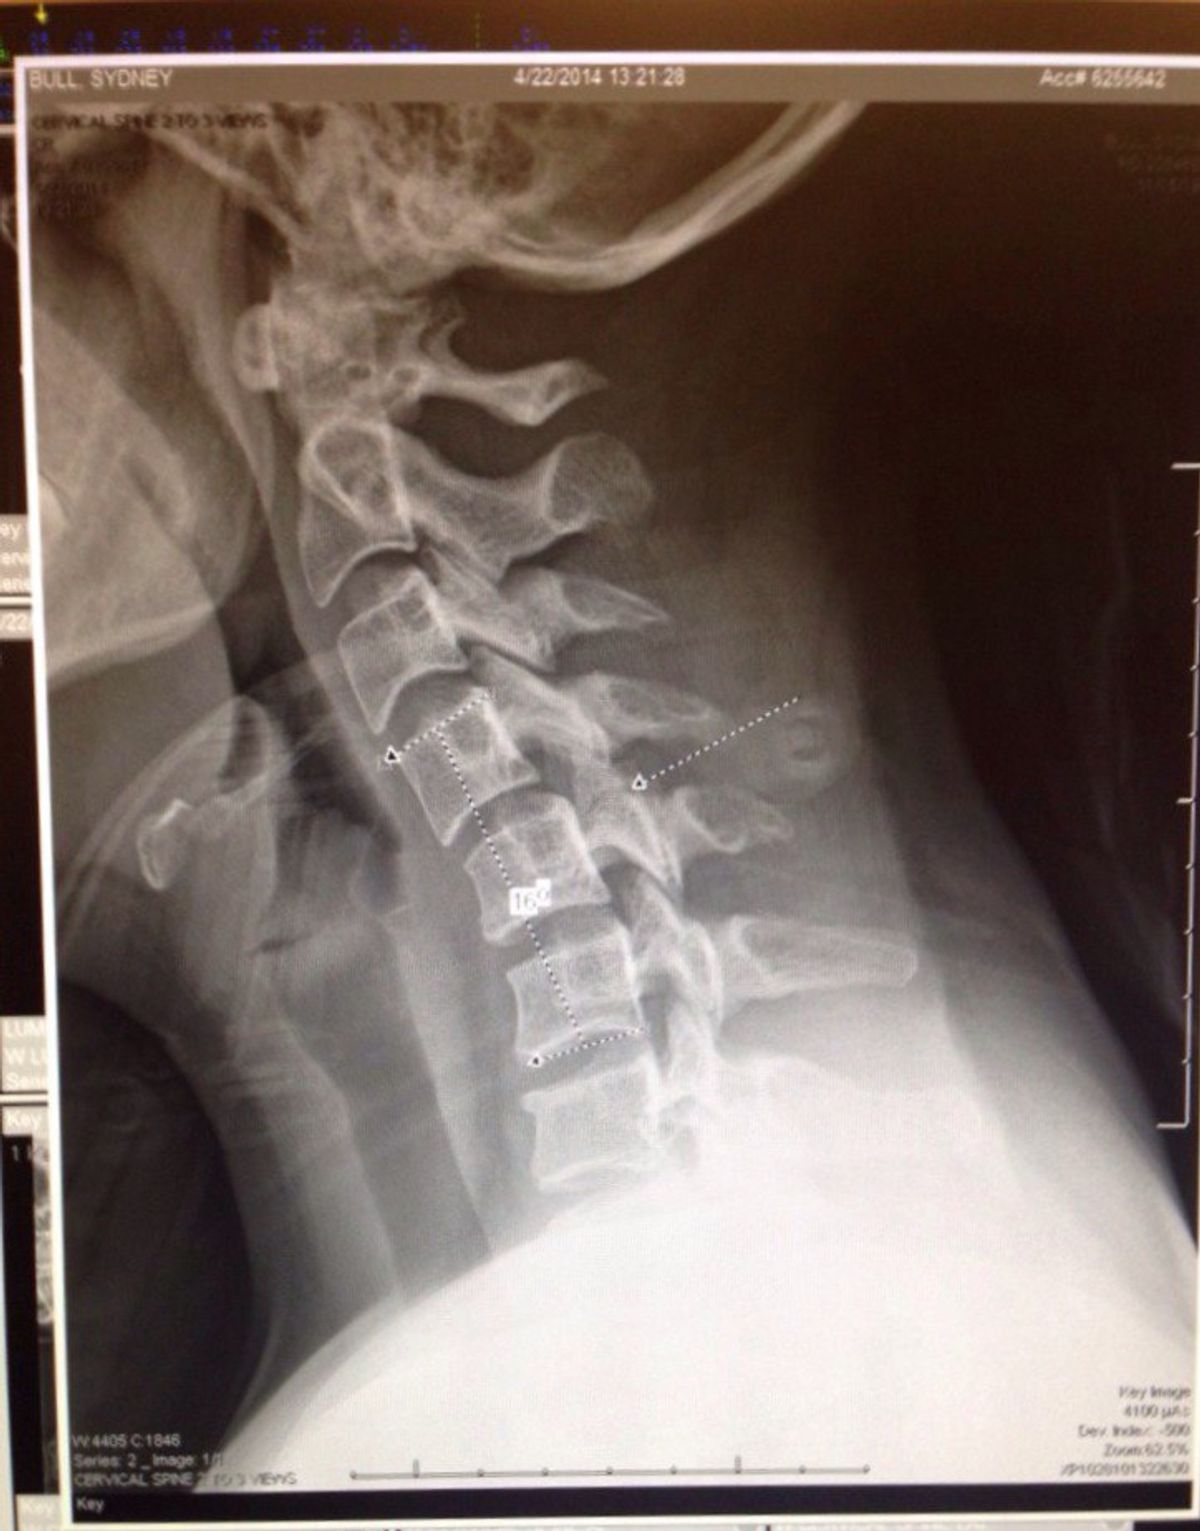

Two years ago I went on a date to a trampoline park with a guy I met on Tinder, and now my life has changed forever. Although my story is bazaar and somewhat humorous, my journey to full recovery has not been easy. After spending all four months of that summer in a neck brace, I grew depressed and unconfident. I was robbed of my independence and I hated that I had become such a burden to everyone around me. Because of the severity of the injury and recovery that it entailed, I had to medical redshirt my junior year of swimming. From that moment on, I viewed my life differently. I personally witnessed a miracle and not only was I lucky enough to walk and live a somewhat normal life, but I was given a second chance to swim and compete at the school I love.